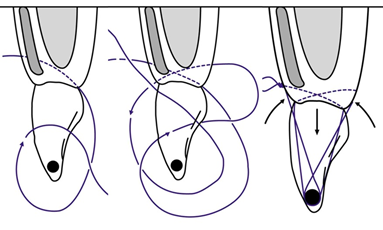

Препарат змили розчином Perio aid 0.12%. З приводу необхідності хімічної обробки кореня зуба під час хірургічних втручань існує декілька точок зору. Ми вбачаємо в цій процедурі можливість додаткової антибактеріальної очистки та покращення візуального контролю перед накладанням швів. Трансплантат введено в реципієнтну ділянку (фото 12) та фіксовано модифікованим підвісним швом (див. схема 3, фото 13).